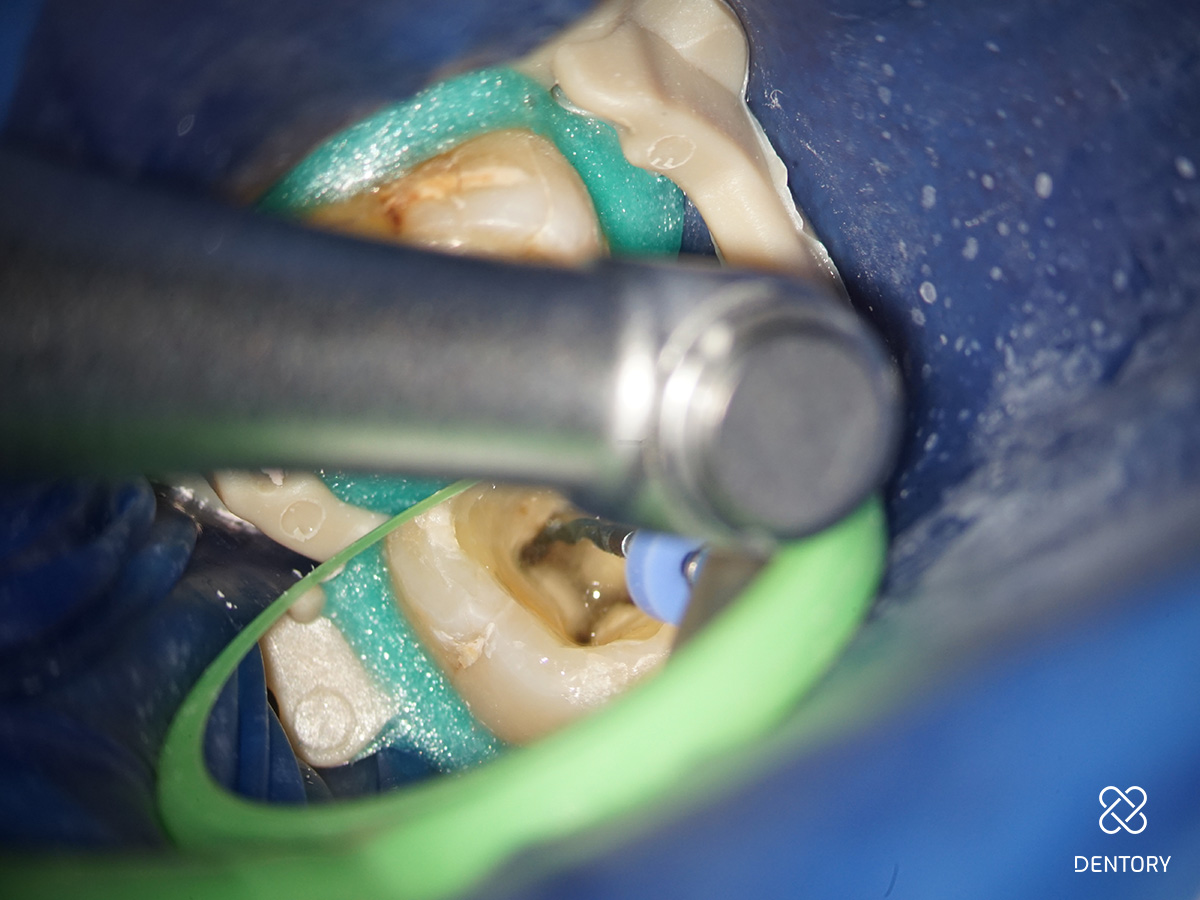

Abbildung 3

Aufbereitung des distalen Kanals: Es ist darauf zu achten, die Kontaktzeit im Kanal kurz zu halten sowie den Kanal abschnittsweise von koronal nach apikal zu bearbeiten. Zusätzlich verhindert eine regelmäßige Rekapitulation mit einer Handfeile bis zur endometrisch bestimmten Länge eine Verblockung des Kanals mit Debris.

Abbildung 4

Nach jedem Einsatz im Kanal ist die Feile visuell auf Deformationen zu überprüfen.